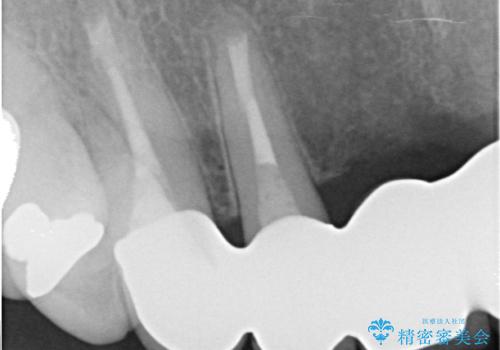

- 仮歯の製作、古い土台(メタルコア)の除去まで行い、根管治療は専門医に依頼

→根管治療終了後、ファイバーコアを築造し、新しいセラミックブリッジを製作した。

一見きれいにはいっているセラミックも、はずして中の状態をみるとひどいことが多い。これは、中の土台の状態や処理のクオリティは、短期的には問題を起こしづらく、患者さんには見えない部分だからです。